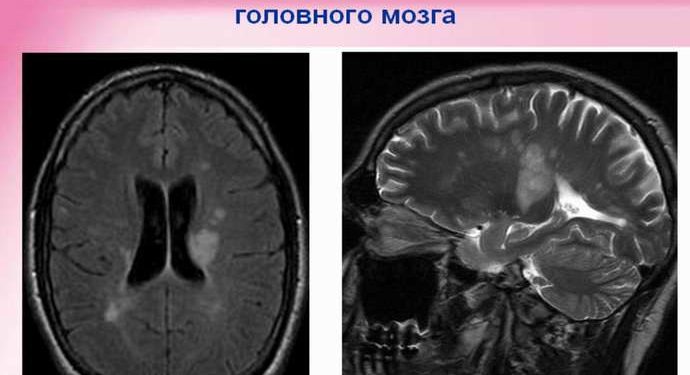

Рассеянный склероз (MS)

Это наиболее распространенное демиелинизирующее заболевание. У каждого из 500 человек есть это. Это аутоиммунное заболевание, которое поражает ваш мозг, спинной мозг и зрительный нерв. Есть четыре типа, от легкой до тяжелой. Это больше влияет на женщин. Это происходит от генетических причин и вещей в вашем окружении.